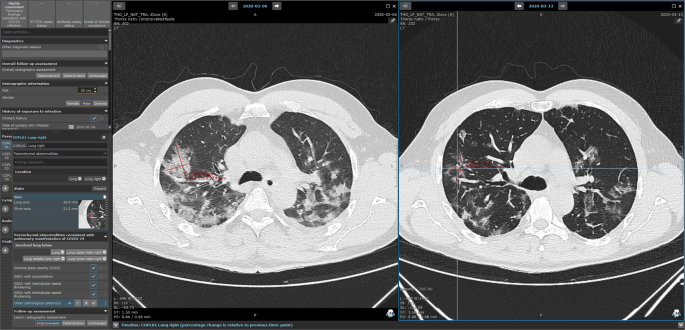

Based on the evidence available back in April 2020, the first version of a COVID-19 Mint EDC was drafted. It is based on the mint LesionTM medical software platform (Mint Medical GmbH, Heidelberg, Germany). Thereby, we enabled structured data annotation directly on primary imaging data from chest computed tomography. In addition, patient history and clinical data are reported in a standardized way in the evidence-based, context-assisted template. As an established software in radiological reporting, mint LesionTM and thus the developed COVID-19 EDC are able to depict disease courses and assess the progression of disease. In order to facilitate rapid, joint data acquisition early in the pandemic, we launched a cloud-based web platform for data to be uploaded, assessed, aggregated and analyzed.

Eight European medical centers including ExploreCOVID centers (BMBF 01KI2054) were willing to prove the feasibility of this concept. They uploaded data from 283 patients, who either had laboratory confirmed Sars-CoV-2 infection or suspected infection based on clinical presentation. Clinicians and radiologists were guided through the whole data annotation process by the tool. Automatic conformity checks of the annotated data and rule-based evaluation were used to improve reporting. A particular strength lies in the permanent linkage of structured imaging-based values including automatic radiomics features with clinical data. The automatic generation of reports for single time points or disease courses of individual patients provided standardized disease assessment according to best scientific knowledge at the time. The developed COVID-19 EDC can be dynamically adapted to new scientific developments without losing any previously collected data. It has continuously been updated and is currently in its third version. In Germany, this reporting concept was adapted and subjected to further development by the nation-wide research initiative RACOON (Radiological Cooperative Network) [https://www.netzwerk-universitaetsmedizin.de/projekte/racoon], in which all university hospitals are participating.